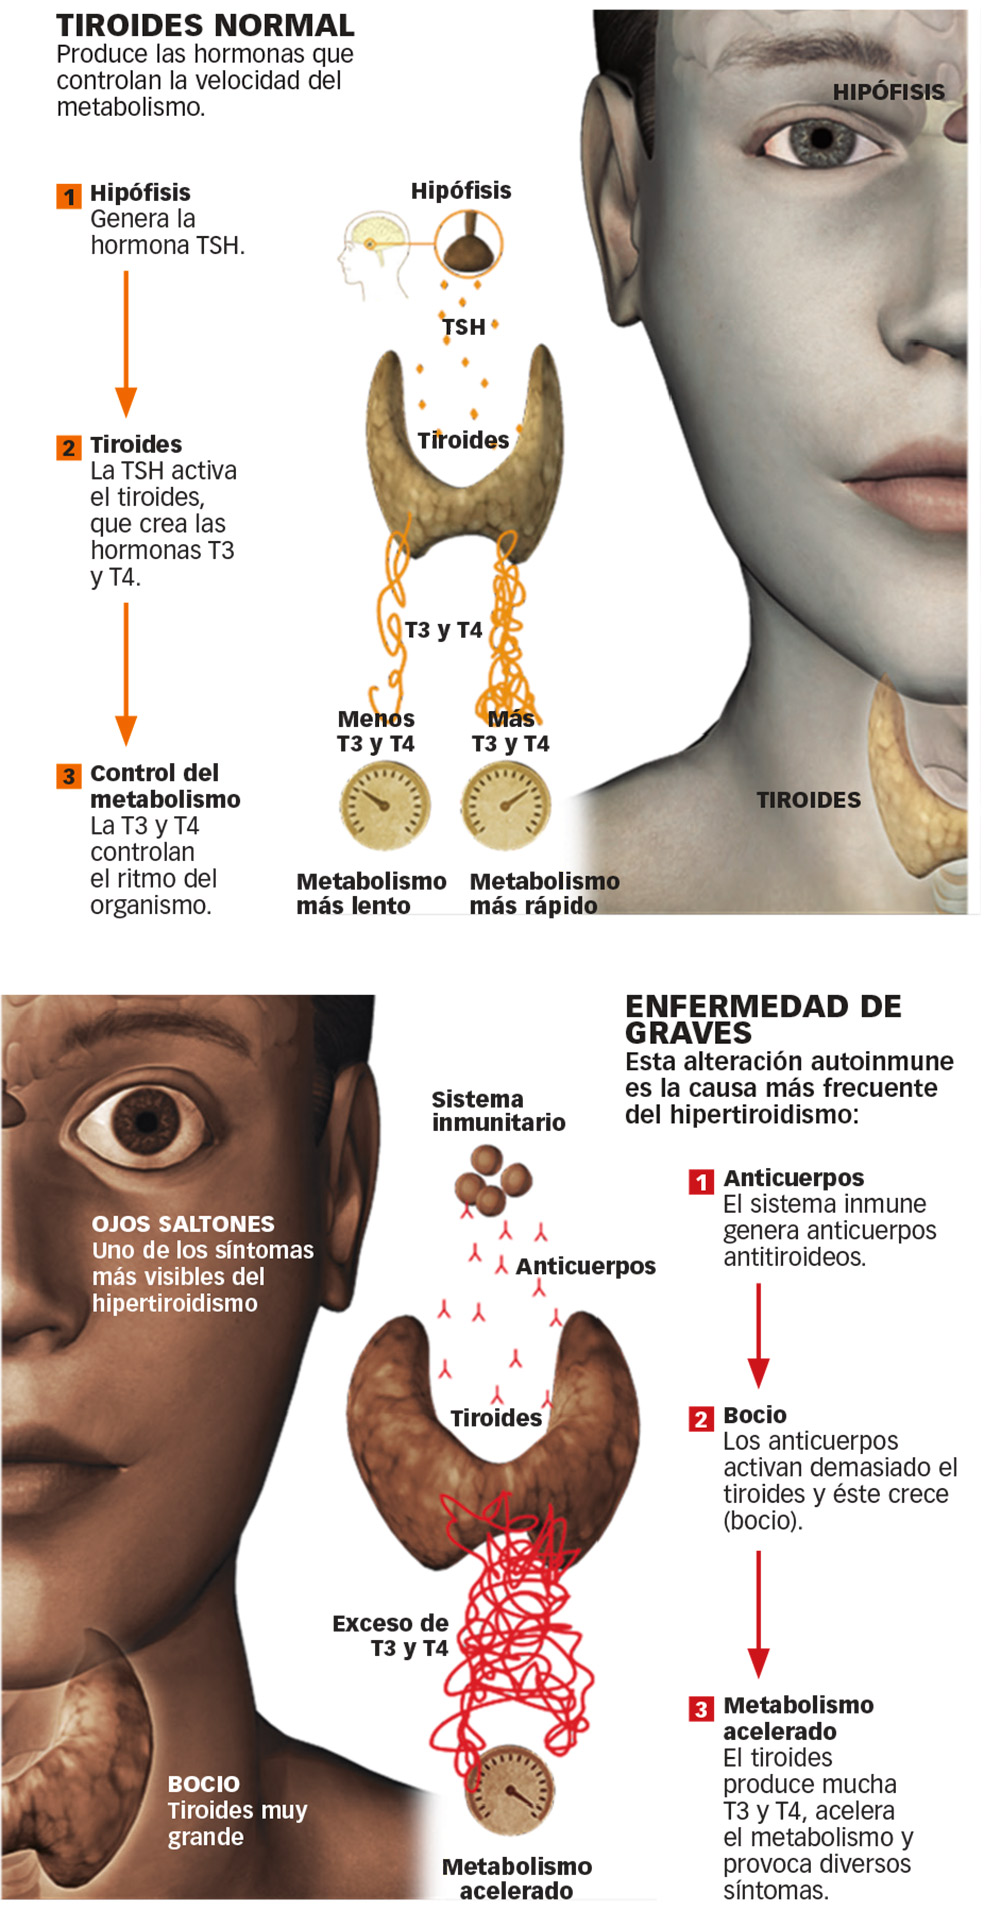

El 9 por ciento restante se debe a la situación contraria: el tiroides está demasiado activo y produce demasiada hormona. Es el hipertiroidismo. Ambas son las disfunciones más comunes, muy por encima de los casos de bocio o de cáncer de tiroides. Y todas ellas son, por causas que no terminan de estar claras, mucho más prevalentes en mujeres.

Los ojos saltones, un síntoma

Tener los ojos saltones puede ser un síntoma de hipertiroidismo. Una reacción autoinmune inflama el tejido y empuja a los ojos. La oftalmopatía tiroidea también puede ocasionar estrabismo, visión doble, sensibilidad y dolor.